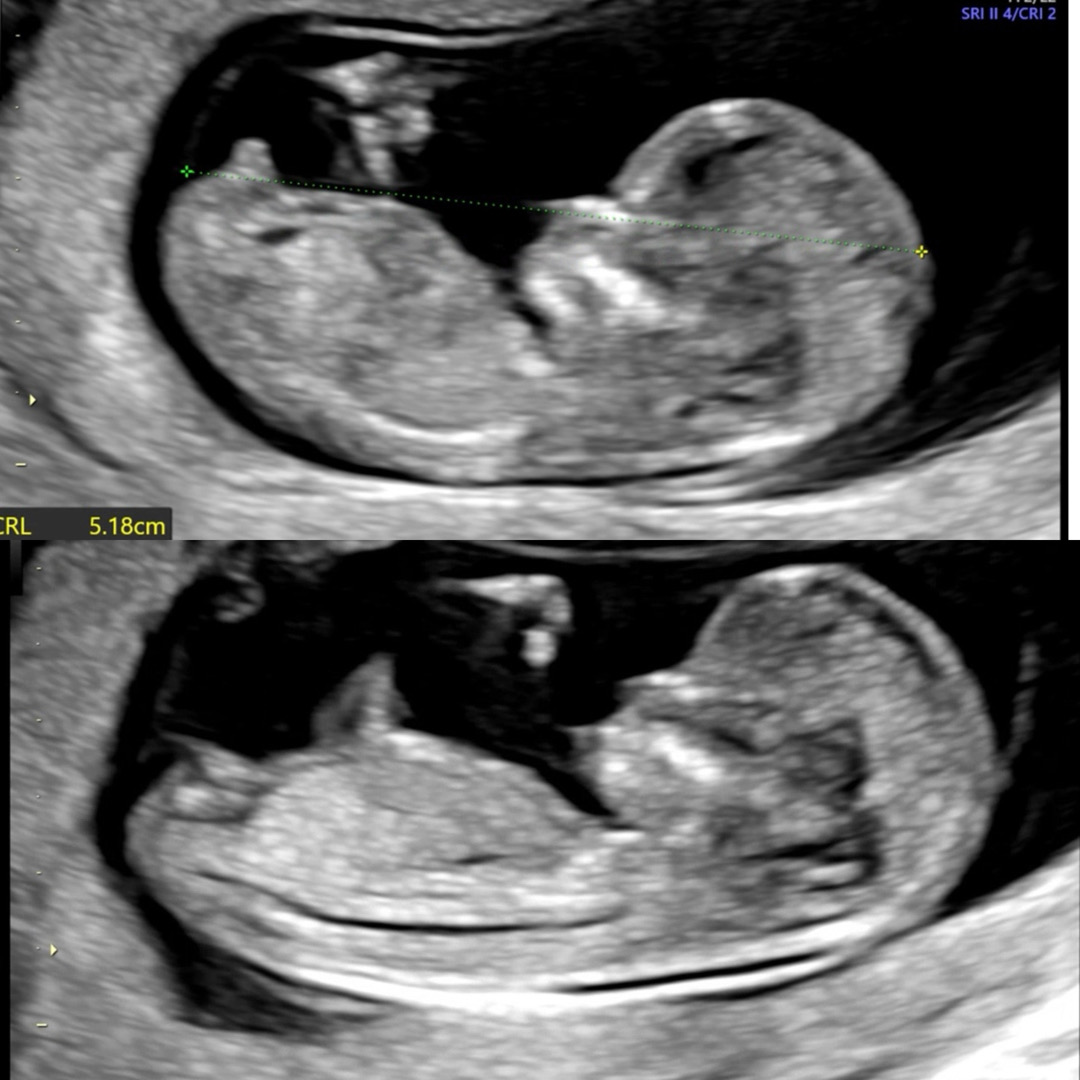

12주차 성별 각도법 봐주세요!!🥹

오늘 12주차1일인데 각도법 봐주실분 계실까요?! 첫째라 너무 궁금해요☺️

아들 같아요 각도가 30도이상 올라갔어요.

아들 같아요 12주 각도법 남자애 사진이랑 첫번때 사진 같아요 아래에 저 올라온 저 방향이요

딸 한표용